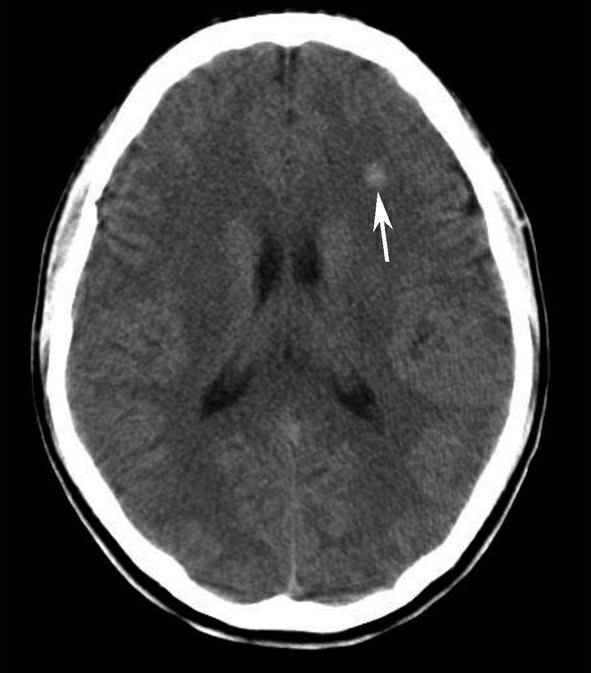

Alberta卒中项目早期CT评分(Alberta stroke program early CT score,ASPECTS)是一种评价急性缺血性卒中患者大脑中动脉供血区早期缺血性改变的简单、可靠、系统化的方法,是常用的脑卒中评定量表之一,可对缺血性病变快速进行半定量评价,有助于判定溶栓效果和远期预后。该评分主要基于CT平扫,具体分区如下(图1-2-76)所示,即选取大脑中动脉供血区2个层面。分区后共10个区域,每个区域记1分。评分时任何区域只要有低密度灶,则扣除该区域得分。正常脑ASPECTS评分为满分(10分),若MCA供血区广泛梗死累及全部区域时,则ASPECTS评分为0分。

图1-2-76 ASPECTS评分脑组织分区

A.在基底节层面(即丘脑和纹状体平面),分为各级分支M 1 、M 2 、M 3 、岛叶(缩写I)、豆状核(缩写L)、尾状核(缩写C)和内囊(缩写IC)后肢等7个区域;B.在基底节以上层面(基底节层面上2cm),包括M 4 、M 5 和M 6 。